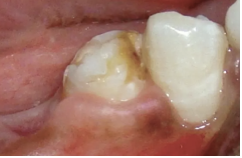

Mom came into the office and said the child had had the first molar extracted before the eruption of the premolar. Based on the following image, what is the likely cause for this discoloration?

A

Turner hypoplasia